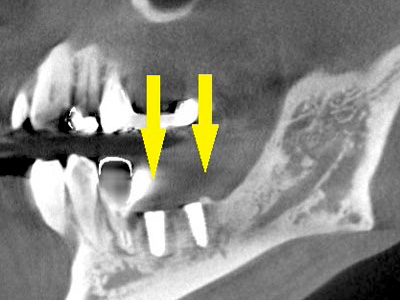

さらに、CTで別な方向から見ると、黄色矢印のように骨が吸収されていて、緑色矢印で示される神経の通る管に迫り、インプラントが埋入できるような骨量はありませんでした。

-

インプラントを埋入するために骨を増やす方法はいくつかありましたが、この場合、患者様ご自身の骨をブロック状で移植するのが最も適していると判断し、自家骨移植術を行ないました。

患者様ご自身の下顎前歯の下方から骨を採取して、骨がなかった部位に移植しスクリューで固定したCT画像です。

黄色矢印部分が、2つの骨片を移植して、固定したところです。 -